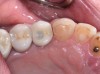

Fig 14. Clear resin cement left on the implant abutment.

Figure 14

Fig 15. Implant abutment following cement removal.

Figure 15